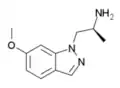

O-methyl-AL-34662 | 1-((S)-6-methoxy-2-aminopropyl)-1H-indazole | 210580-60-2 |